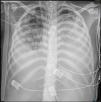

Mujer de 19 años, con antecedente de miopatía de Steinert, intubada por distrés respiratorio grave tras laparotomía exploradora por seudooclusión intestinal. En aspirado traqueal, E.coli sin mecanismos de resistencia. Muy mala mecánica pulmonar (compliance inferior a 2ml/cmH2O) y sin respuesta a maniobra de prono, se canula ECMO veno-venoso y, ante las altas presiones en la vía aérea con 4ml/kg de peso ideal, se cambia ventilación por ventilación con liberación de presión en la vía aérea (APRV): presión alta 15cmH2O; tiempo alto 6s; tiempo bajo 0,3s. Inicialmente 10ml de volumen espirado. La evolución radiográfica se muestra en las imágenes (fig. 1: día0; fig. 2: día2; fig. 3: día5). Este caso es un ejemplo de cómo la ventilación por APRV mientras aseguramos el intercambio gaseoso con el ECMO puede ser útil en el manejo de pacientes con distrés respiratorio refractario.